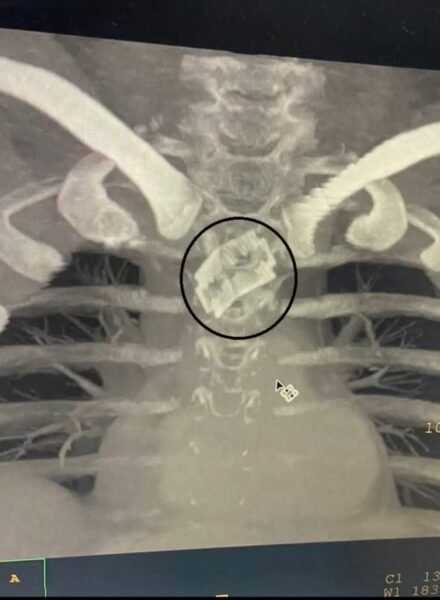

मामला कुछ इस प्रकार से है कि 26 वर्षीक पुरुष भूलवश खाने के साथ रेज़र ब्लेड निगल गए। खाने की नली में फंसे धारदार ब्लेड की वजह से मरीज़ के जीवन पर बन आई। श्री महंत इन्दिरेश अस्पताल के नाक कान गला रोग विभाग के डाॅक्टरों ने प्रारम्भिक जाॅचां में पाया कि ब्लेड श्वास नली के निकट महत्वपूर्ण खून की सबसे बड़ी नस के काफी नजदीक अटकी हुई है।

श्री महंत इन्दिरेश अस्पताल के नाक कान गला रोग विभाग के डॉक्टरों ने 26 वर्षीय पुरुष की खाना खाने की नली में फसे रेजर ब्लेड को निकालकर मरीज को नया जीवन दिया। श्री महंत इन्दिरेश अस्पताल के असिस्टेंट प्रोफेसर व ईएनटी सर्जन डॉक्टर शरद हरनोट ने सीनियर रेजिडेंट डॉ. फातमा अंजुम के साथ मरीज की सफल सर्जरी की और एंडोस्कोपी द्वारा पूर्ण रेजर ब्लेड को खाने की नली से बाहर निकाला। मरीज के माता पिता ने डॉक्टरों व श्री महंत इन्दिरेश अस्पताल का आभार जताया। ऑपरेशन अत्यधिक जटिल था। ऑपरेशन के बाद मरीज को नाक की नलकी द्वारा उपचार एवम खाना शुरू किया गया। ऑपरेशन के बाद मरीज बिल्कुल ठीक है।

डॉ. शरद हरनोट ने बताया कि 26 वर्षीय मरीज के परिजन को श्री महंत इन्दिरेश अस्पताल में उपचार के लिए लेकर आए। मरीज के पिता ने जानकारी दी कि अज्ञात परिस्थिति में मरीज ने रेजर ब्लेड को निगल लिया। उन्होंने बताया कि वो उत्तराखण्ड के कई अन्य बड़े अस्पतालों में उपचार के लिए गए लेकिन मरीज की समस्या का समाधान नहीं हुआ और रेफर कर दिया गया। इसके बाद वह अपने पुत्र को लेकर श्री महंत इन्दिरेश अस्पताल आए। श्री महंत इन्दिरेश अस्पताल के असिस्टेंट प्रोफेसर व ईएनटी सर्जन डॉक्टर शरद हरनोट ने सीनियर रेजिडेंट डॉ. फातमा अंजुम के साथ मरीज की सफल सर्जरी की और एंडोस्कोपी द्वारा पूर्ण रेजर ब्लेड को खाने की नली से बाहर निकाला। मरीज के माता पिता ने डॉक्टरों व श्री महंत इन्दिरेश अस्पताल का आभार जताया।